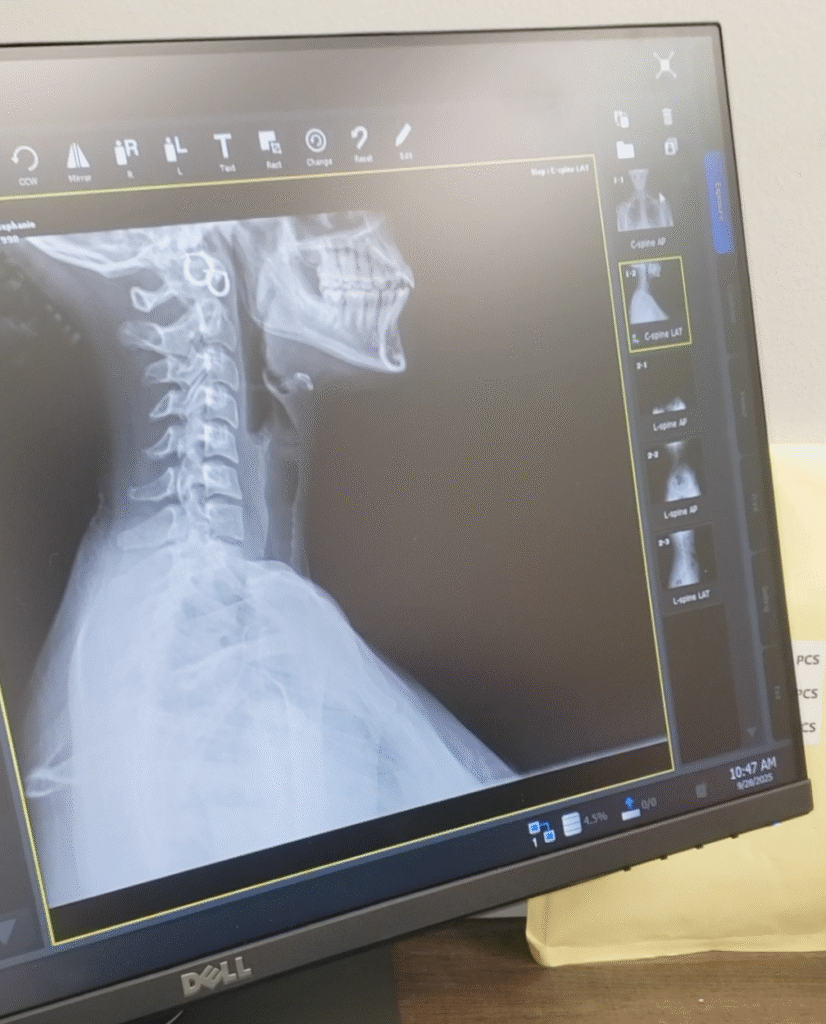

In-Office X-Ray

To See Is to Know

With advanced digital X-ray equipment and strict safety protocols, we gain clear insight into your spine, joints, and skeletal structure – so we can treat with confidence rather than guesswork. At Star Chiro, Dr. Wei is fully licensed and trained to operate radiographic systems, enabling us to deliver more precise, customized care.

Precise Imaging for Smarter Care

Every spine tells a story- and at Star Chiro, we make sure we’re listening. Using advanced digital X-ray imaging, Dr. Wei identifies the exact source of discomfort before care begins. These images help confirm spinal alignment, detect hidden issues, and guide every adjustment for safer, more accurate results.

Expert Evaluation, Clear Explanation

After your X-rays are taken, Dr. Wei reviews them with you one-on-one, explaining what she sees and how it relates to your symptoms. With clear visuals and simple language, you’ll understand what’s happening inside your body – empowering you to take an active role in your healing journey.

Safe Technology, Trusted Expertise

Our state-of-the-art imaging equipment delivers exceptional clarity while keeping radiation exposure extremely low-adhering to modern FDA safety standards. Dr. Wei is fully licensed and trained in chiropractic radiogra- phy, ensuring every image is taken responsibly and interpreted with precision. Because seeing clearly is the first step toward feeling better.